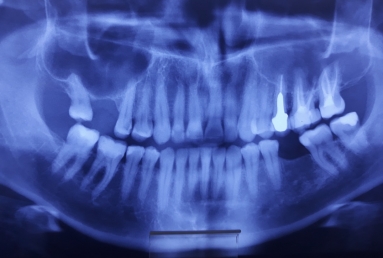

This patient has advanced dental abrasion due to bruxism ( clenching the teeth during the night). this is why the bite is modified and the frontal teeth are shorter. First stage of the treatment is wearing a night guard to relax the muscles and the temporo-mandibular jaw.

The final porcelain veneers for all frontal maxillary teeth are completed with tooth whitening and changing some composite fillings in lower frontals. On the lower left side a dental implant is inserted, on the upper right side external sinus lift is done. the treatment will be finalised with another upper implant, then two crowns on implants.